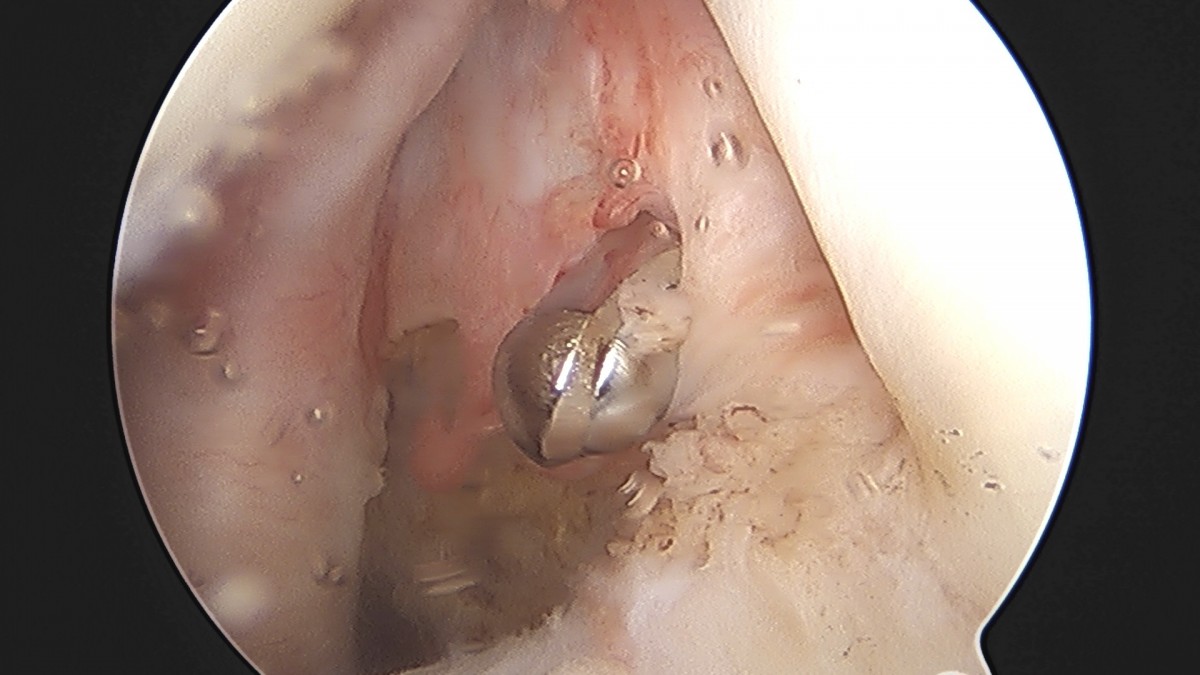

이재상원장님 어깨 견봉하 감압술 및 관절낭 이완술 음성O 환자

작성자 최고관리자 댓글 0건 조회 805회 작성일 25-09-16 15:32